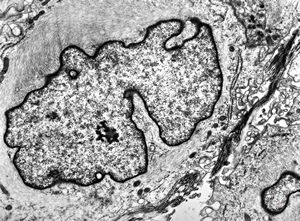

M, 62y. | mitosis … angiomatous tumor, v.s. Kaposi sarcoma

M, 62y. | angiomatous tumor, v.s. Kaposi sarcoma